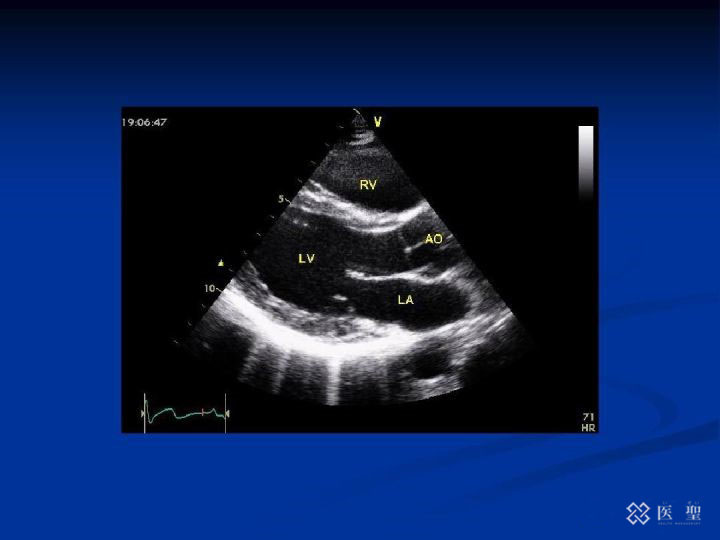

心脏超声波影像

心脏精密检查:心脏超声波检查,通过超声波观察心脏活动的检查;颈动脉超声波检查进行颈动脉成像的检查;PWV(脉搏波传播速度)检查传播到动脉的脉搏波的速度;BNP是从心脏分泌出的一种激素,心脏负担加重时呈高值,可以找出心电图检查无法查到的心脏疾病。